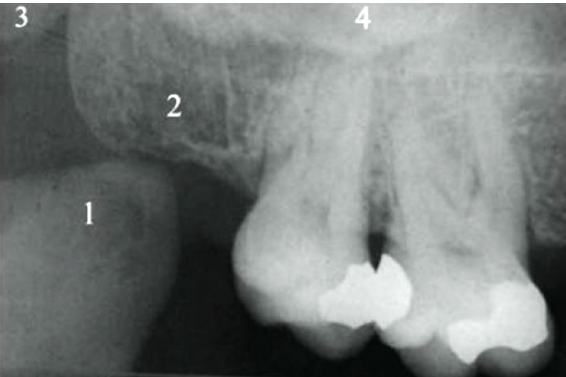

Observe a imagem abaixo de uma radiografia periapical de molares superiores:

Assinale a alternativa que corresponde à nomenclatura da estrutura anatômica marcada como 1 na imagem.